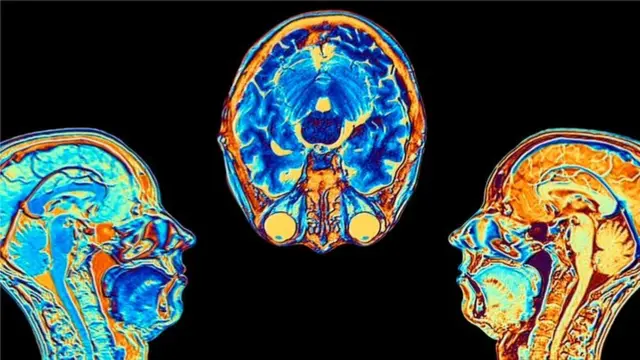

እቲ ኣብ ኣእምሮ ዝግበር ስካን፡ ሕማም ኮቪድ ኣብ ነዊሕ እዋን ኣብ ሓንጎል ከኸትሎ ዝኽእል ሳዕቤን እንተሎ ይርኢ ኣሎ። ፕሮፌሰር ኣለን፡ "ተመራመርቲ ፡ እቲ ቫይረስ ኣብ እተፈላለዩ ኣካላት ሰብነት ከስዕቦ ዝኽእል ሳዕቤን፡ ካብቲ ኣብ ፈለማ ዝተሓስበ ዝተፈልየ እንተኾይኑ ብዕምቆት ንኺምርምሩ ክሕግዞም እዩ" በለ ።

እቲ ቫይረስ ኣብ ልብን ኩሊትን ጥራሕ ዘይኮነ፡ ኣብ አእምሮ እውን ጽልዋ ይፈጥር ምህላውን ሓያሎ ሰባት ድሕሪ ሕማም ኮቪድ ምዕፋን ናይ አእምሮ ምርሳዕን ናይ ኣትኩሮ ጸገም፡ ሕማም ርእስን ጭንቀትን የጋጥሞም ከም ዘሎ ሓቢሮም።

ኣብ ኢምፐርያል ኮሌጅ ለንደን ኒውሮሳይክሊስት ፕሮፈሰር ፖል ማቲውስ፡ " እቲ ኣብ ሓንጎል ዝግበር ዘሎ ስእሊ ብዛዕባ ሓፈሻዊ ነገራት ሓንጎል ይነግረና ኣሎ። እቲ ስእሊ፡ እቲ ሕማም ኣብ ሓንጎል ቀጻሊ ነድርን ሳዕቤን ዘኸትል ምዃኑን፡ ምናልባት እውን ነቲ ናይ ሓንጎል ነርቭ ክጭብጦን ክሽምርሮን ከምዝኽእል ምልክታት ኣርእዩ ኣሎ።